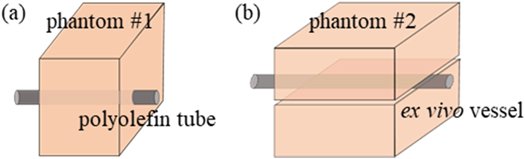

The characteristics of the fabricated vascular phantom was similar to the blood vessels and surrounding tissues. The vascular phantom could mimic the blood and vessel. A blood vessel (vessel mimic tube or ex vivo vessel) was located 15 mm below the top surface of the phantom. Polyolefin tube, as a vessel mimic material, was embedded into phantom #1 (figure 1). Its diameters were chosen at 1.9 and 3.2 mm. Its acoustic and thermal parameters can be found in table 1. The ex vivo blood vessel was compressed by two pieces of phantom #2 (see figure 1). Blood mimic material was composed of 225 ml deionized and degassed water, 25 ml glycerin solution and 0.5 g glass beads. Its acoustic and thermal parameters were similar to those of the blood (Kim et al 2017) (see table 1). The blood mimic material was stirred uniformly and poured into a 250 ml infusion bag. Two straight tube connectors were fixed at both ends of the ex vivo vessel. The tube dedicated for peristaltic pump, the infusion bag and the vessel were connected by the connectors (see figure 2). The peristaltic pump (Longer Precision Pump, Hebei, China) was assembled with silicone tubing to drive the circulation of blood mimic material. At the pump speed of 100 rounds per minute (rpm), the flow rate of vascular mimic tube was measured, and they were respectively 14.4 cm s−1 (1.9 mm diameter) and 10.4 cm s−1 (3.2 mm diameter). The flow rate of ex vivo vessel was 5 cm s−1 at 50 rpm pump speed.

Figure 1. The structure of phantom #1 (a) and phantom #2 (b).